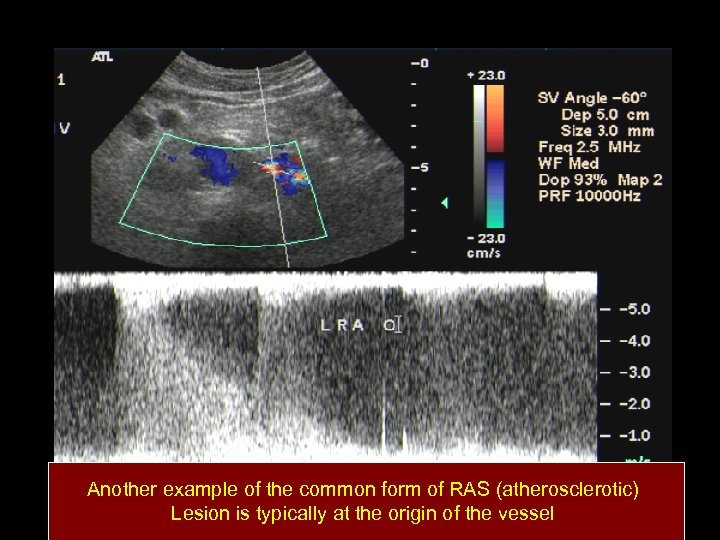

Another example of the common form of RAS (atherosclerotic) Lesion is typically at the origin of the vessel